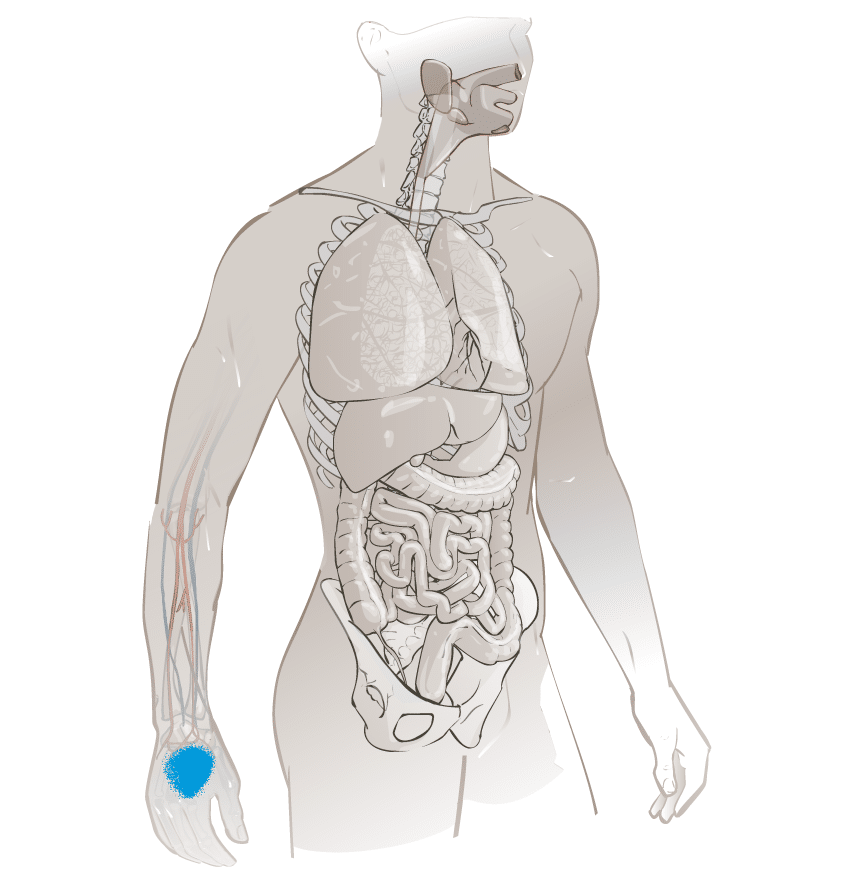

Pour l’Homme (6), les portes d’entrées (5) sont directement liées aux modes de transmission : voie respiratoire ou aérienne pour une transmission par inhalation, voie cutanée ou transcutanée pour une transmission par inoculation ou contact direct avec les muqueuses, et voie orale ou digestive pour une ingestion.

Voie cutanée/transcutanée